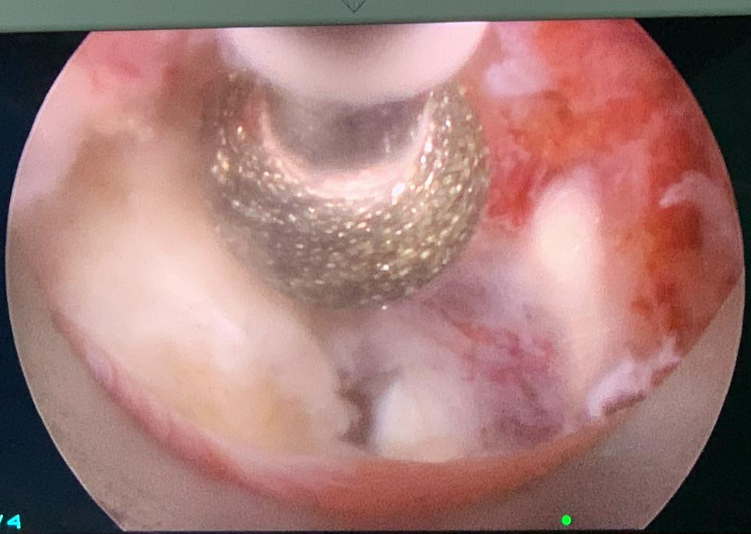

內視鏡手術則是在下背開一公分左右傷口,使用內視鏡在椎體之間作業,切除突出的椎間盤讓被壓迫的神經獲得減壓。

脊椎微創內視鏡手術

脊椎微創內視鏡手術